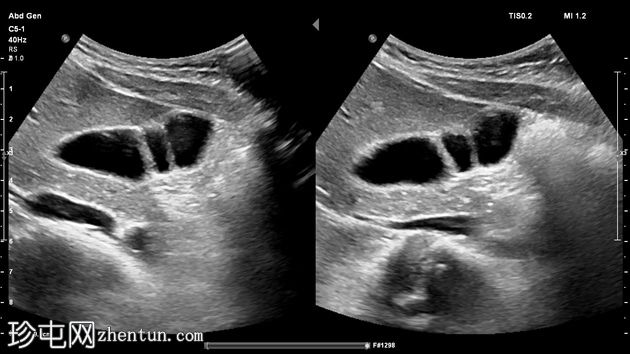

纵切面

横切面

两个高回声隔膜将胆囊腔分隔成三个腔室。未见胆泥、结石、息肉、憩室或任何炎症病变。

另见左肾静脉位于主动脉后方。

这是在一位年轻

健康

女性中偶然发现的典型分隔性胆囊的

影像

学表现。

交界皱襞很常见,不应与胆囊隔膜混淆。胆囊隔膜通常较薄,横切胆囊腔,将其分隔成多个腔室,这些腔室可能通过细小的孔隙相互连通。弗里吉亚帽是交界皱襞的典型例子。